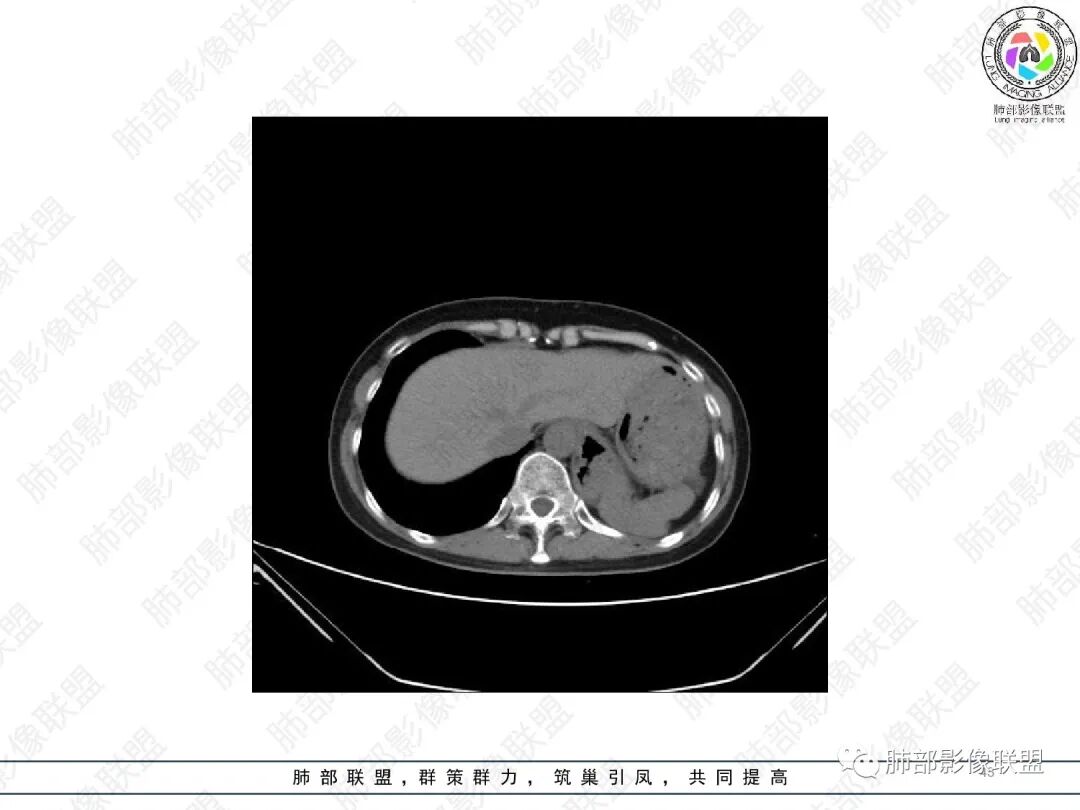

2.胸部CT:右肺上叶及中叶不规则块状影,沿支气管走行方向指套样影,支气阻塞湖嵌塞,腔内可见高密度影。灶周可见磨玻璃,外围见结节影及树芽征。左肺体积缩小,见不规则条索影、胸膜增厚,纵隔牵拉左移。